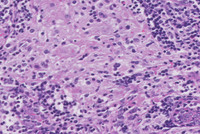

Figure 1-H&E

The low power H&E image demonstrates multifocal pale eosinophilic areas and higher power demonstrates that these pale areas comprise accumulations of large bland histiocytes with abundant pale eosinophilic cytoplasm with intermingled lymphocytes and plasma cells.  Higher power demonstrates that these histiocytes have small but distinct nucleoli.